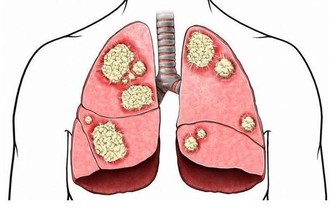

酒精被吸收到血液之後,首先會經肝臟分解為乙醛,這是一種對身體各組織細胞有著非常強的刺激作用的物質。

喝酒有好處嗎? 醫生:有,但還是要勸你把酒戒掉,這是為啥?

以血管為例來舉例說明一下,類似於鐵生鏽一樣會使血管內皮的細胞受損,而血管內皮實際上是血管的內保護層,受損之後,血管內表面的天然屏障便會被破壞了。

在這時,血液當中的脂肪等大分子物質就會從血管內皮的破損處進入並沉積下來,那麼什麼是動物脈粥樣硬化呢?動脈粥樣硬化,實際上就是血管當中沉積了大量的脂肪,當這些沉積的脂肪集結成團的時候,就會形成斑塊,此時心腦血管疾病也就會發生。

我們再來了解一下飲酒對肝臟方面的影響,肝細胞在乙醛的強烈刺激下會表現得非常興奮,也會合成更多包括甘油三酯、高密度脂蛋白等在內的脂肪,甘油三酯為大量積存在肝細胞當中,此時脂肪肝便發生了,長久以往會使肝細胞持續受到損傷。

過多的脂肪進入到血管之後,因乙醛損傷了血管內皮,而更容易沉積在血管的內皮之下,促進與加速了血管病變的發生。